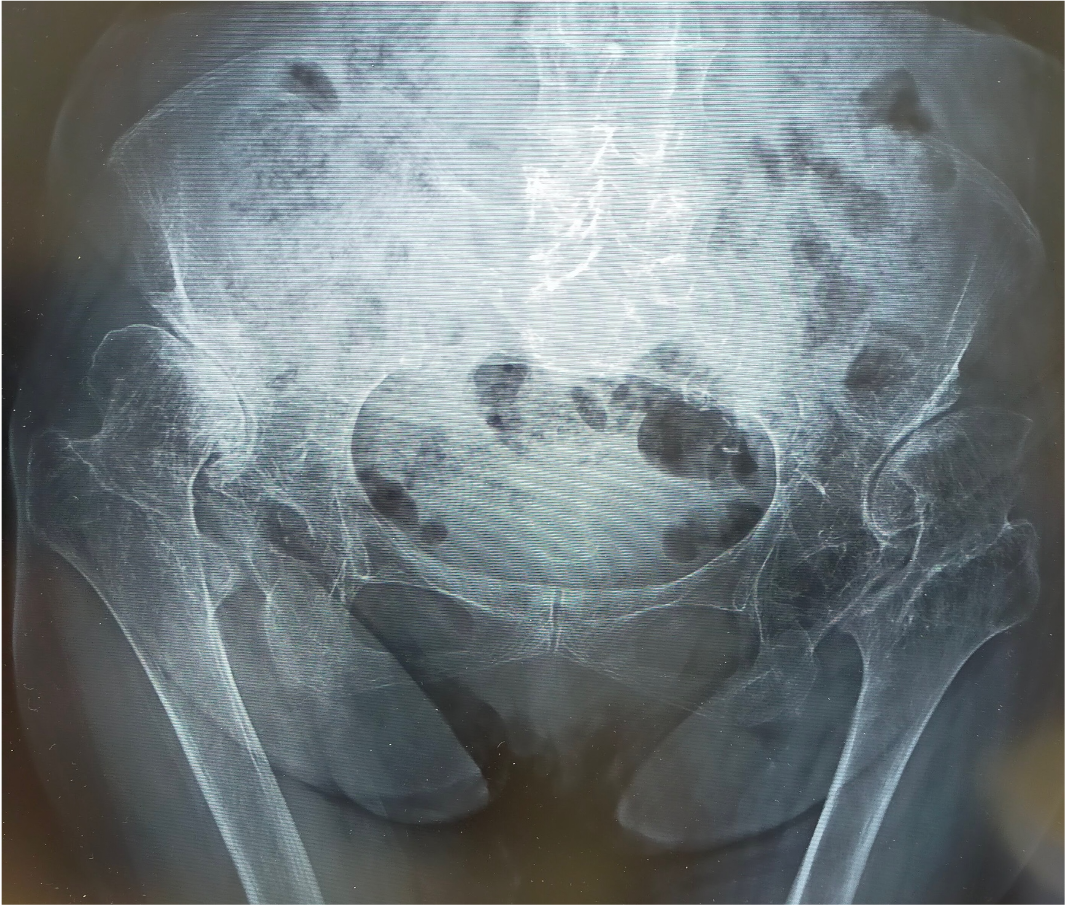

〈手術前のレントゲン〉

両側とも股関節は上外側に脱臼し、腸骨部に新たな関節が形成されています(二次臼蓋)。股関節の変形に伴い、関節の動きも大きく制限されており、左膝の関節症(X脚変形)も生じていました。左右の脚の長さに差が生じるために、骨盤は傾き、背骨も変形しています。

脊椎・骨盤〜股関節〜膝はそれぞれが連動して機能しており、単一の障害ではありません。全体のバランスを考えて治療法を考える必要があります。

このように変形が高度な症例では、通常の人工股関節での治療は難しく、特殊な人工股関節置換術が必要となります。

今回の症例では、まず左股関節症に対して大腿骨短縮骨切り併用THAを行いました。